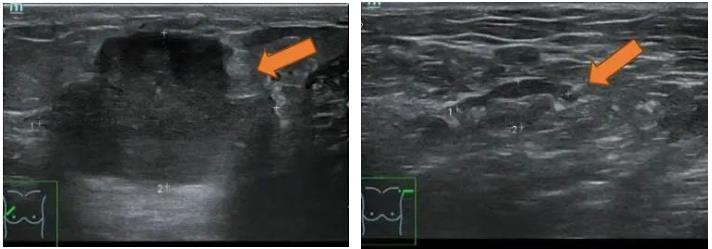

(2 cycle 后)2021.8.31 乳腺超声示:右乳10点实性肿块 44.9mm×13.1mm。

图5. 乳腺超声